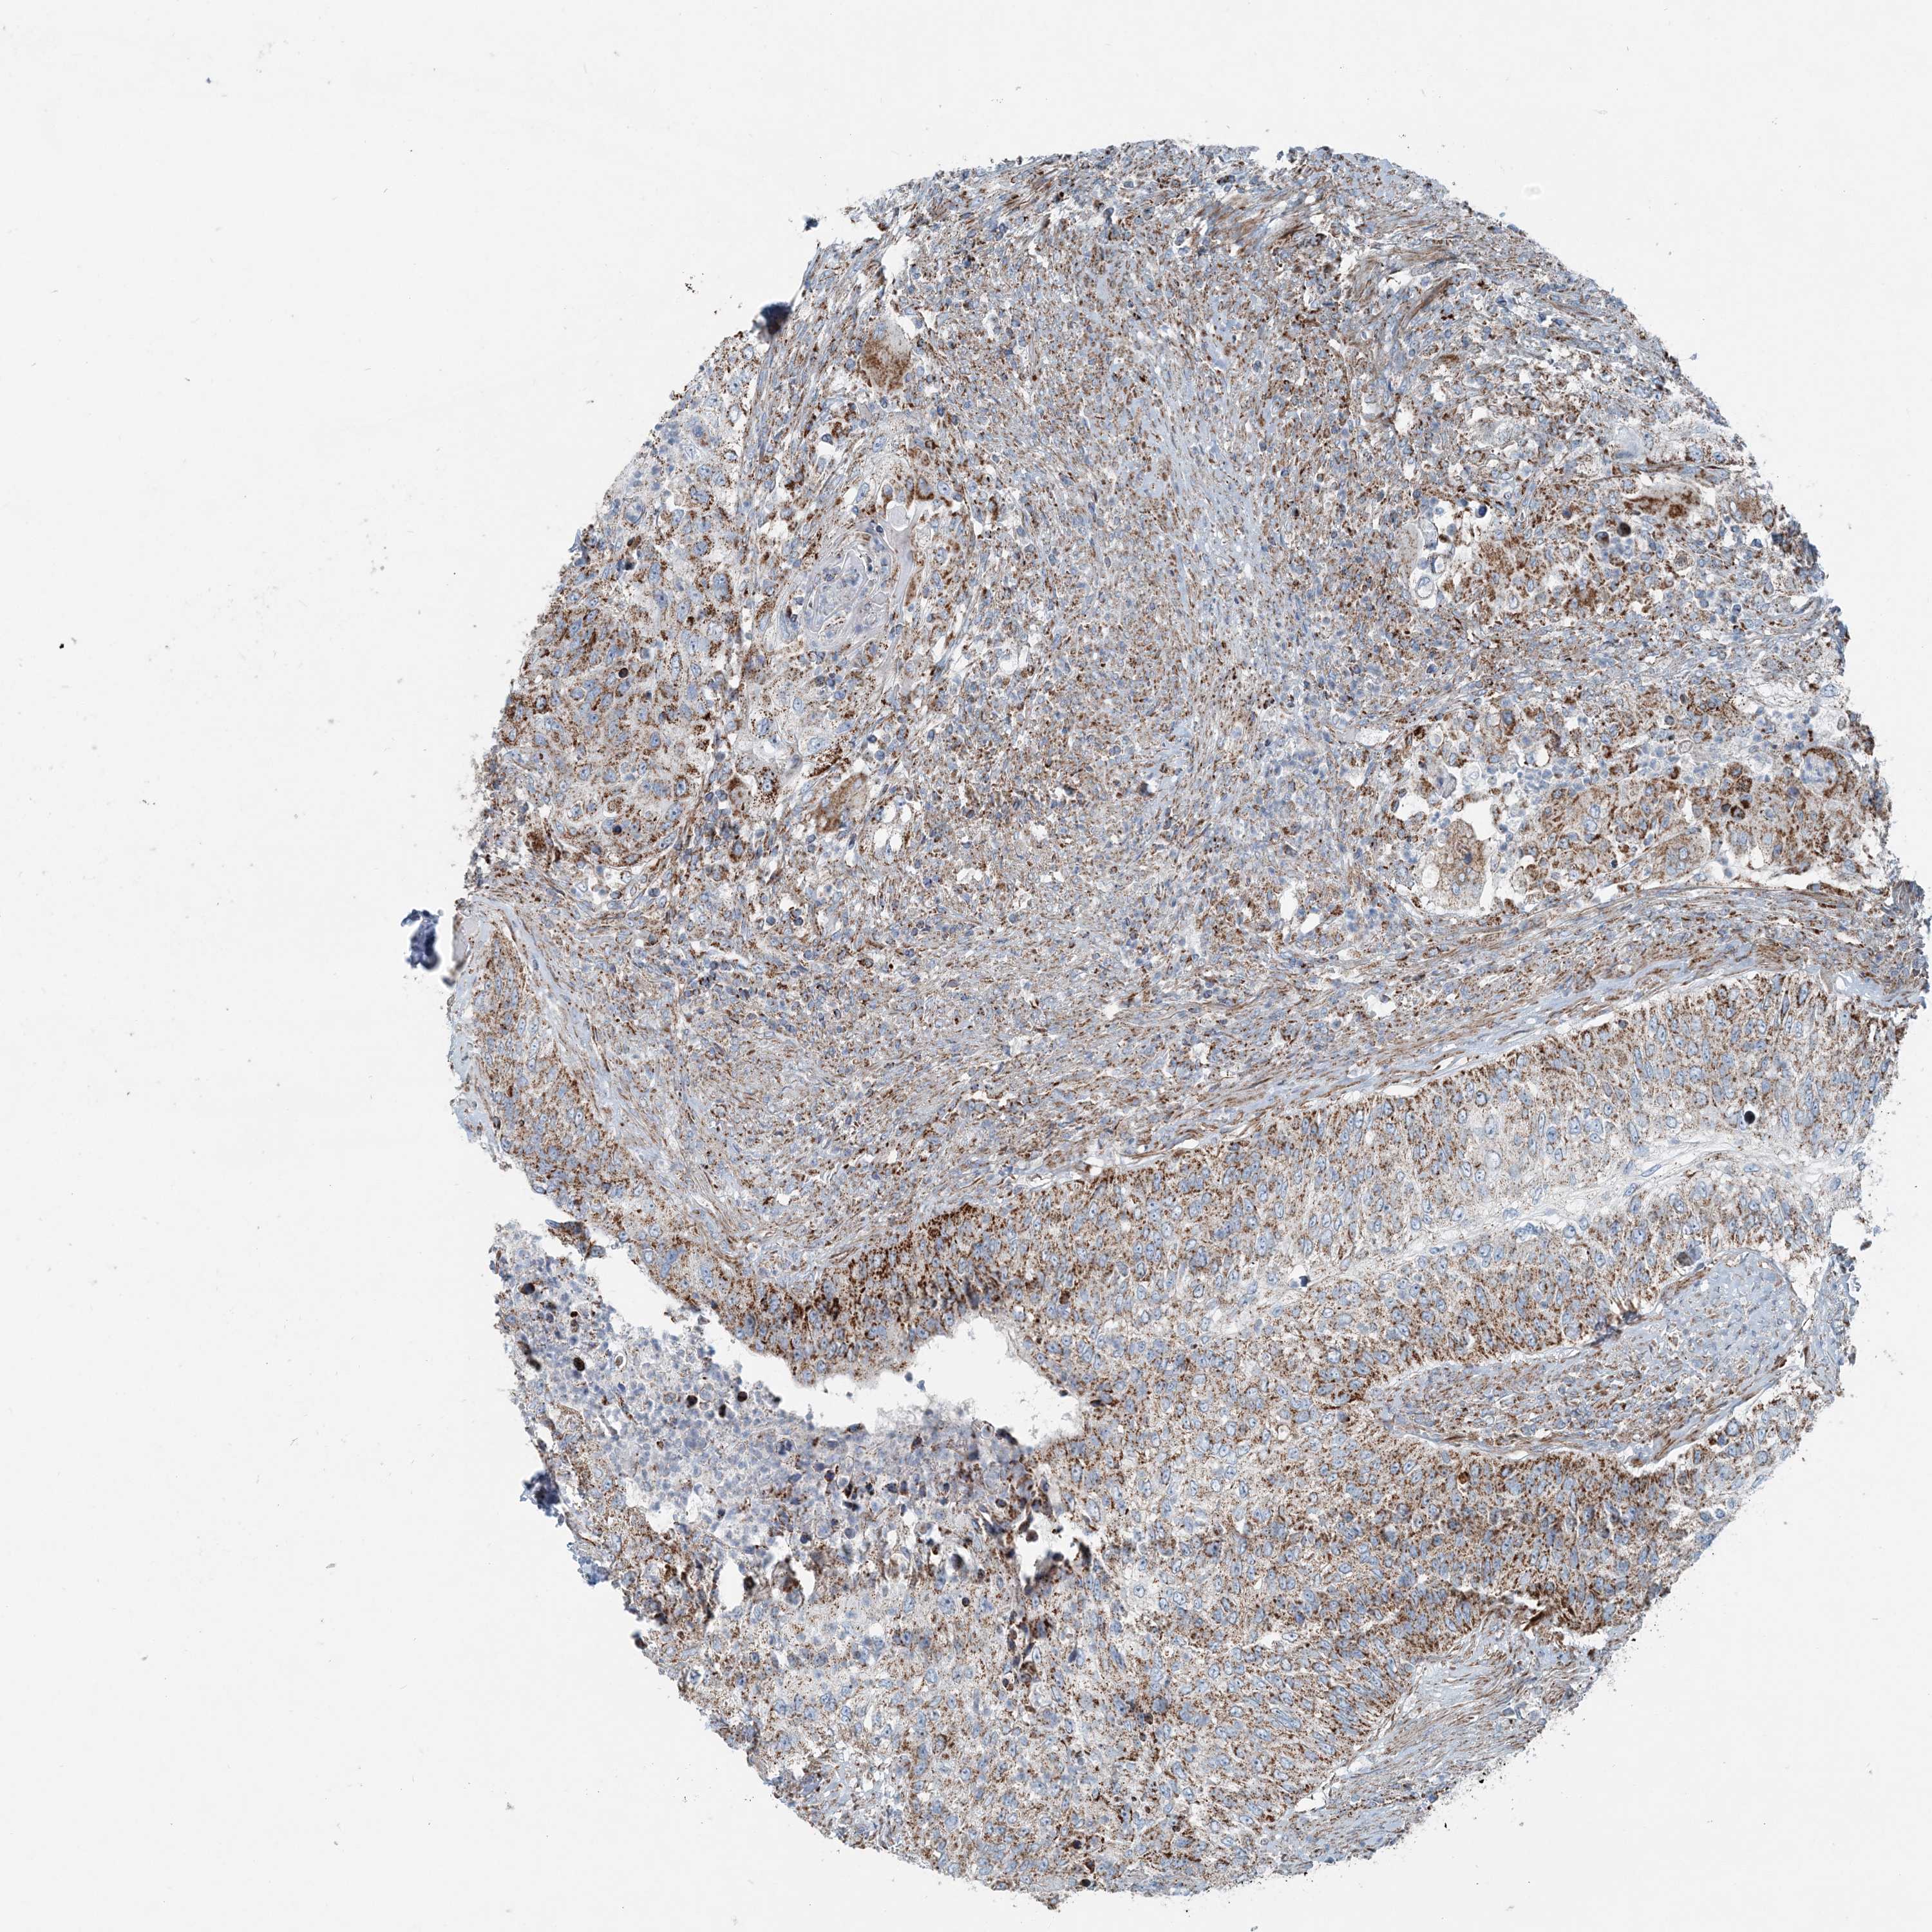

UROTHELIAL CANCER - Protein expressioni

A mouse-over function shows sample information and annotation data. Click on an image to view it in a full screen mode. Samples can be filtered based on level of antibody staining by selecting one or several of the following categories: high, medium, low and not detected. The assay and annotation is described here.

Antibody stainingi

Antibody staining in the annotated cell types in the current human tissue is reported as not detected, low, medium, or high, based on conventional immunohistochemistry profiling in selected tissues. This score is based on the combination of the staining intensity and fraction of stained cells.

Each image is clickable and will lead to virtual microscopy that enables deeper exploration of all samples and also displays staining intensity scores, fraction scores and subcellular localization as well as patient and tissue information for each sample.

Antibody HPA036714

Antibody HPA036715

Staining

High

Medium

Low

Not detected

Intensity

Strong

Moderate

Weak

Negative

Quantity

>75%

75%-25%

<25%

None

Location

Nuclear

Cytoplasmic/membranous

Cytoplasmic/membranous,nuclear

Urothelial carcinoma, High grade